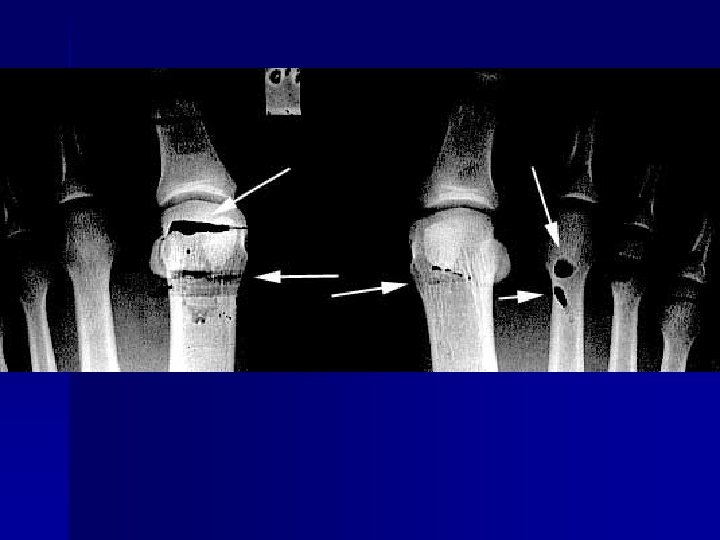

Exposure Artifacts Motion n Improper patient position n Wrong screen-film match n Poor film/screen contact n Double exposure n Warped cassette n Improper grid position n

Artifact

Name & cause of this?